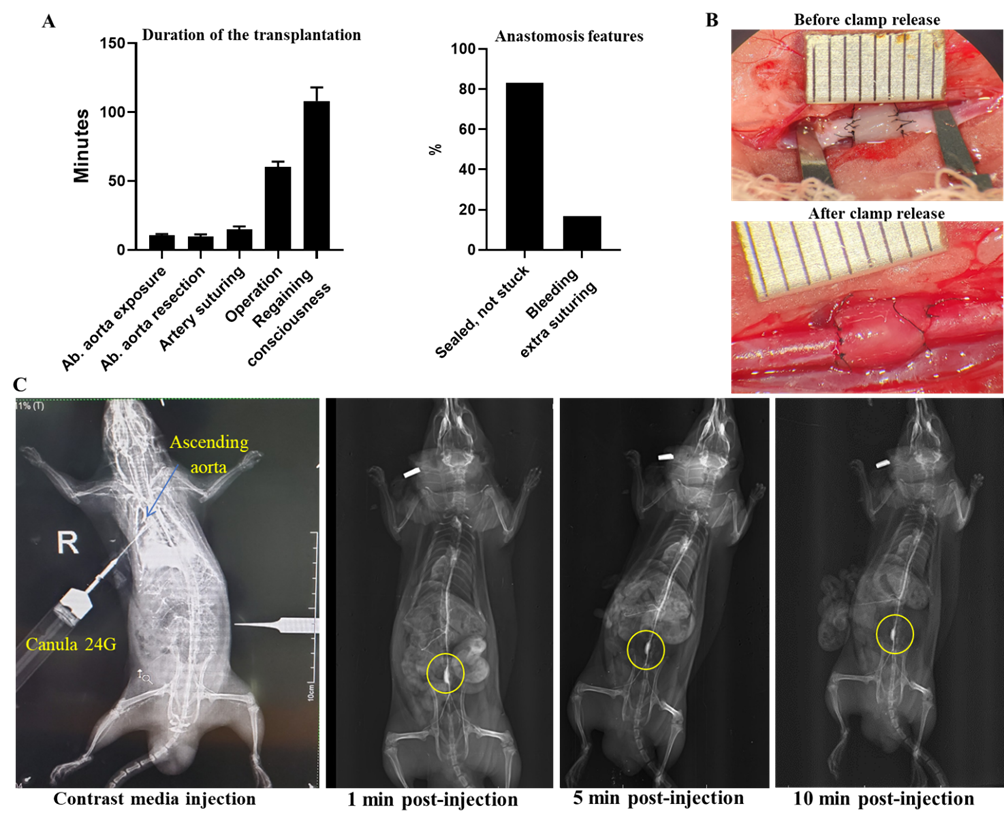

Thứ nhất, rất nhiều nghiên cứu đã chứng minh các tế bào từ mô dây rốn cũng như nhiều thành phần cấu tạo của dây rốn, bao gồm cả động mạch sau khử dây rốn có tính sinh miễn dịch thấp, do đó có thể ghép đồng loài một cách hiệu quả. Thứ hai, việc sử dụng mạch dây rốn tươi vẫn chứa các thành phần tế bào và cấu trúc nguyên vẹn của mạch máu có thể tránh được các hiện tượng phình mạch gây ra bởi sự suy yếu cấu trúc thành mạch và hiện tượng huyết khối do thiếu lớp nội mạc. Bên cạnh đó, việc sử dụng dây rốn tươi sẽ khắc phục được nhược điểm về thời gian cần để xử lý khử tế bào của mạch máu, có thể đáp ứng nhanh chóng nhu cầu ghép mạch. Vì vậy, nhóm nghiên cứu đã tiến hành ghép động mạch dây rốn người với động mạch chủ bụng dưới thận chuột cống trắng Wistar. Nội dung nghiên cứu này đã được Hội đồng đạo đức Học viện Quân y thông qua trong khuôn khổ của dự án.

Sau một quá trình nghiên cứu và thử nghiệm, chúng tôi đã xây dựng được một quy trình xử lý mạch tiền ghép và quy trình ghép mạch dị loài từ động mạch dây rốn vào động mạch chủ bụng dưới thận chuột cống trắng thành công. Các động mạch dây rốn sau khi thu nhận và xử lý tiền ghép không gây kích thích tăng sinh tế bào T khi tiếp xúc với các tế bào bạch cầu đơn nhân của máu chuột cống, không kích thích biểu hiện các yếu tố chỉ thị trạng thái hoạt hóa của tế bào T (còn gọi là tế bào lympho T – là một loại bạch cầu thuộc dòng tế bào lympho, đóng vai trò quan trọng trong hệ thống miễn dịch đáp ứng của cơ thể) như IL1-β, IFN-α, và TNFα. Hơn nữa, phân tích giải phẫu bệnh cho thấy chỉ có sự đáp ứng viêm nhẹ khi mạch dây rốn được cấy vào lớp mỡ dưới da chuột cống sau 30 ngày. Những kết quả này cho thấy, động mạch dây rốn tươi có tính sinh miễn dịch thấp, phù hợp cho việc ghép trên chuột cống.

Kết quả ghép dị loài cho thấy, 100% chuột ghép mạch dây rốn người (10/10) đều có khả năng sống trên 4 tuần sau ghép. Đáng chú ý, không nhận thấy hiện tượng tắc mạch hay huyết khối xảy ra trong mạch ghép dựa trên các kết quả siêu âm định kỳ sau 3, 7, 21, và 30 ngày sau ghép. Thêm vào đó, mặc dù có sự không hoàn toàn phù hợp về kích thước, do đường kính mạch dây rốn lớn hơn động mạch chủ của chuột cống, tương tự như các báo cáo đã công bố, nhưng trong nghiên cứu này, kết quả siêu âm cho thấy đường kính trong lòng mạch khá ổn định theo thời gian, không thấy sự tăng rõ rệt về kích thước như trong nghiên cứu của Gui và cộng sự. Đồng thời, lưu lượng máu lưu thông trong mạch ghép khá tương đồng với động mạch chủ chuột tại hai đầu nối mạch. Đánh giá vi thể, các chỉ số sinh lý, hóa sinh, và phản ứng miễn dịch cho thấy mảnh ghép hòa hợp với cơ thể nhận và thực hiện chức năng như các mạch máu bình thường của cơ thể. Các kết quả đánh giá hoạt động chức năng vận động của chuột ghép cho thấy sự tương đồng với đối chứng trong suốt quá trình thí nghiệm. Quy trình ghép và chuột ghép dị loài đã được nhóm nghiên cứu đăng ký sáng chế với Cục Sở hữu trí tuệ (đã được chấp nhận đơn và đang trong quá trình xem xét cấp bằng).